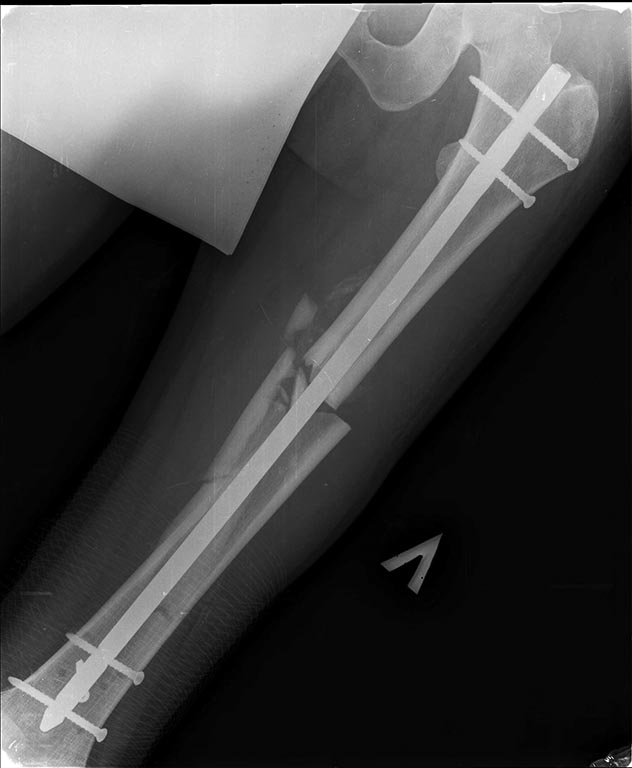

Добрый день уважаемые коллеги. Вашему вниманию представляю пациента(мужчина, 30 лет). Тяжелая сочетанная травма 7 мес. назад. Из скелетной травмы: открытый перелом бедра, открытый перелом дистального метаэпифиза левого плеча, закрытый перелом шейки левого плеча). Все повреждения были прооперированы. Бедро синтезировано штифтом Остеомед d-11мм. Раны зажили первично. Пациент после выписки впервые появился на контрольный осмотр ч/з 7 месяцев. Жалобы на боли в левом бедре при нагрузке, ощущение подвижности в месте перелома. Передвигается без дополнительных средств опоры. Локально: отека левого бедра нет, п/операционные рубцы без признаков воспаления. движения в суставах левой н/конечности в полном объеме, безболезненны.( все снимки, первичные, после операции и на сегодня прилагаю). основной вопрос, тактический, чем лучше выполнить реостеостеосинтез. У нас в наличии имеется: из штифтов Остеомед d-12мм, старый набор Синтез с канюлированными штифтами максимальный d-14мм., пластины LC-DCP, аппарат Илизарова. В плане 2 варианта: 1) удаление проксимальных блокирующих винтов(сломаный тоже), фиксация бедра спице-стержневым аппаратом из 2-х опор и компрессия в аппарате. 2)удаление металлоконструкции, и выполнение реостеосинтеза с рассверливанием( учитывая очень широкий канал) с установкой винтов поллеров в дистальном отломке. Жду ваших предложений и мнений. Спасибо заранее

С возросшей регулярностью на форуме обсуждаются «беспричинные» случаи несращения переломов после интерлокинга. В постах больше внимания уделяется обсуждению тактике дальнейшего лечения. Причём в подобных случаях предлагаемые варианты не отличаются многообразием и ограничиваются либо таким же остеосинтезом только стержнем большего диаметра, либо пластинкой с костной пластикой либо внеочаговой фиксацией. К сожалению, почти всегда остаются без анализа возможные причины, приведшие к несращению. А жаль. Ведь вероятность сращения после интерлокинга приближается к ста процентам, и точно установленная причина, почему это не произошло в положенные сроки, может подсказать тактику дальнейшего лечения. С моей точки зрения, безусловной причиной несращения перелома бедренной кости в обсуждаемой случае является оставшаяся подвижность между проксимальным и дистальными фрагментами после остеосинтеза. На это указывает и сам больной. Причём очаг нестабильности расположен в проксимальном костном фрагменте между ним и проксимальным концом стержня. Хотя на первый взгляд кажется, что вся проблема в дистальном костном отломке, точнее в отсутствии стабильности между ним и дистальным концом стержня из-за значительной разницы в диаметрах стержня и костномозгового канала. На последних рентгенограммах чётко видна костная мозоль между латеральным кортикальным слоем и стержнем на входе в костномозговой канал дистального отломка. Она говорит об эффективности дистального блокирования тремя блокирующими винтами в полифокальных плоскостях. И на сегодня биомеханическая система дистальный отломок – стержень работает как единое целое. Формируется новый костномозговой канал в дистальном отломке по ходу дистального конца стержня за счёт образования костной мозоли между латеральным кортикальным слоем и стержнем. И этот формирующийся костномозговой канал точно соответствует диаметру стержня, что является дополнительным фактором, стабилизирующим дистальный конец стержня. Поэтому, с моей точки зрения, не имеют смысла предложения, направленные на введение каких-либо металлоконструкций, уменьшающих размер костномозгового канала дистального отломка. Да и сделать это технически при такой рентгенологической картине крайне сложно, если вообще возможно. Что касается проксимального блокирования. Крайне неудачно проведен самый проксимальный блокирующий винт. Если авторы рассчитывали на последующую динамизацию (что, при таком переломе крайне неразумно), то его надо было проводить по верхнему краю овального отверстия. Если предполагалось статическая фиксация на протяжении всего периода сращения, то было бы разумнее его провести по нижнему краю овального отверстия. Тогда нагрузка при передвижении больного распределялась бы на оба проксимальных блокирующих винта, что снизило бы вероятность их перелома. Я уже писал в предыдущих постах с похожими случаями. Два блокирующих винта во фронтальной плоскости, один из которых проведен через овальное отверстие, не могут обеспечить стабильность во фронтальной плоскости, если костномозговой канал на выходе из проксимального отломка не соответствует диаметру стержня. И это, с моей точки зрения, служит наиболее частой причиной несращения. И это же служило причиной частых несращений при фиксации тонкими стержнями без рассверливания костномозгового канала. В данном случае мы бы рассверлили канал до диаметра канала на выходе из проксимального отломка (13-14 мм) и имплантировали бы стержень такого же диаметра как последнее сверло. Отдаю предпочтение протезированию всей длины бедренной кости с дистальным блокирование в мыщелках. Лучший вариант, с моей точки зрения, – реконструктивный стержень с проксимальным блокированием в шейке бедра двумя винтами. Хотя допустим и обычный стержень с расположением винта в овальном отверстии по его нижнему краю. Режим фиксации, безусловно, статический.

Непохоже. Вверху он нормально держался, и внизу центрального отломка канал неширокий. Подвижность явно была, но скорее всего, больше за счет расколотого и длинного периферического отломка, винты-то далеко, а рычаг длинный. В сочетании с неустранненным смещением по ширине, отсутствием кортикальной аппозиции по латеральной стенке даже достаточно активного костеобразования здесь не хватило, чтобы стабилизировать отломки.